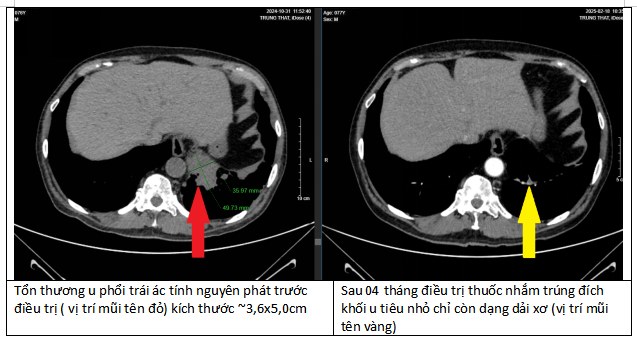

Sau 4 tháng điều trị, các khối u tại phổi, não, xương của bệnh nhân đều thu nhỏ lại. Đặc biệt tại phổi, khối u đã biến mất tới 90%. Đây là một kết quả kinh ngạc, tạo ra kỳ tích cho bệnh nhân.

“Bằng việc tuân thủ điều trị theo đúng phác đồ, bệnh nhân có kết quả hoàn toàn bất ngờ “thần kỳ” sau 4 tháng điều trị”, bác sĩ Duy Anh chia sẻ.